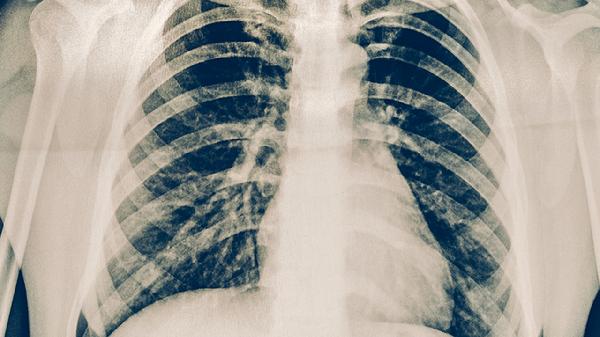

若病变范围广泛或合并多重感染,病情可能较重。高龄、存在慢性心肺疾病或免疫功能低下者更易出现这种情况。病原体可能包括耐药菌、病毒或真菌,导致肺部出现大面积实变或胸腔积液。患者常表现为持续高热、呼吸困难、意识模糊等全身中毒症状,甚至引发脓毒症或呼吸衰竭。此类情况需住院接受静脉抗生素如注射用头孢曲松钠联合阿奇霉素治疗,必要时需氧疗或呼吸机支持。

肺炎性病变的诊断需结合胸部影像学与实验室检查,治疗应严格遵循医嘱。日常需注意保暖、避免吸烟、保持室内通风,接种流感疫苗和肺炎疫苗有助于降低感染风险。若出现咳脓痰、胸痛或呼吸急促症状加重,须立即就医。